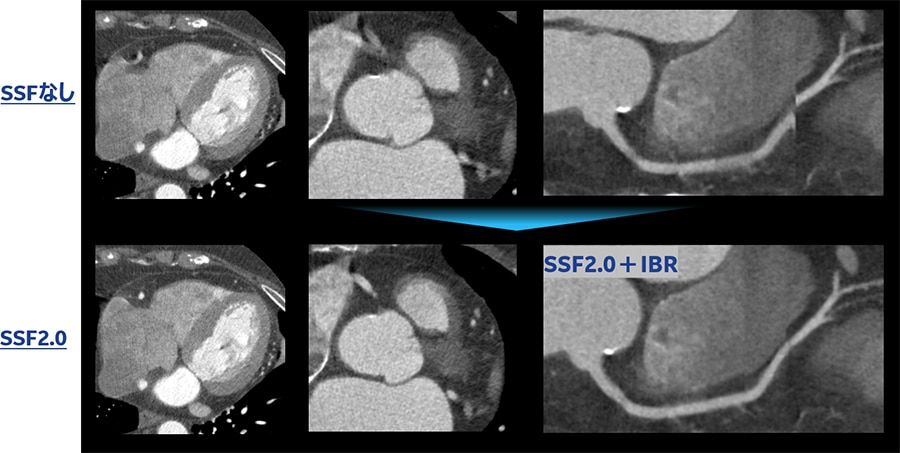

Fig.7 SSFなし、SSF、SSF2.0比較例